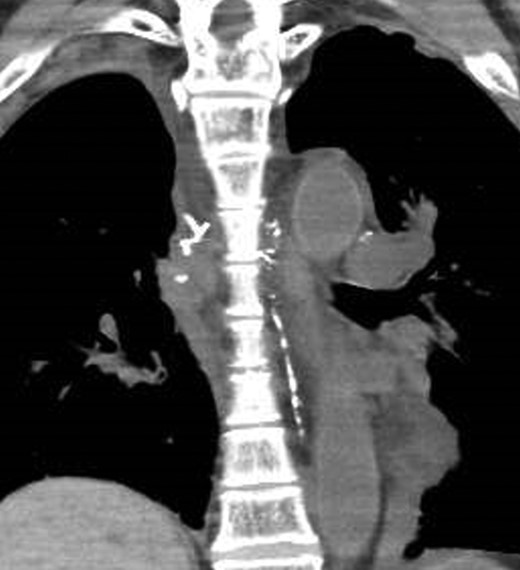

A 67-year-old man was referred to our hospital after transbronchial biopsy confirmed a diagnosis of non-small cell lung cancer. His physical examination findings and laboratory data were unremarkable. CT revealed a right upper lobe mass (diameter, 4.1 cm) in the apical portion; and thus, invasion of the right subclavian artery was suspected. On clinical staging, the tumor was T4N0M0, Stage IIIA. He underwent right upper lobectomy and mediastinal lymph node dissection via median sternotomy. Complete resection was achieved without concomitant resection of the right subclavian artery. The histological diagnosis was squamous cell carcinoma (pT3aN0M0, Stage IIB). Two drainage tubes were placed in the right thoracic cavity, and a total milky fluid volume of 2000 ml was drained on postoperative day (POD) 2. The volume of chylous drainage did not reduce with total parenteral nutrition. On POD 4, right-sided video-assisted thoracic surgery was performed 1 hour after intake of ice cream, to identify the site of chylous leakage. On intraoperative observation, multiple leakage sites were noted between the trachea and superior vena cava, and these sites were clipped and sealed with fibrin glue. However, the thoracic duct could not be identified in the right posterior mediastinum. After this surgical procedure, the volume of chylous drainage did not decrease. In addition, on POD 5 the patient complained of dyspnea. A chest X-ray revealed left pleural effusion, and a drainage tube was inserted into the left pleural cavity. LAG was performed to identify the leakage site, and the total amount of drained effusion from both sides was 3200 ml/day on POD 6 (2 days after the reoperation). The right inguinal lymph node was punctured with a 23-gauge needle under ultrasound guidance, and a total lipiodol volume of 7 ml was slowly injected under fluoroscopic guidance. CT after LAG revealed that the thoracic duct was located on the left side (Fig. 1). However, a day after LAG, the leakage site could not be clearly identified. Additionally, CT showed accumulation of lipiodol at the anterior mediastinum, which suggested the presence of chylous leakage from the thoracic duct tributaries in the anterior mediastinum (Fig. 2). Bilateral pleural effusion gradually decreased after LAG, and a low-fat diet was started on POD 20. The right and left chest drainage tubes were removed on POD 21 and POD 28, respectively. The patient was eventually discharged 30 days after the first surgery (23 days after LAG). CT performed 2 months after LAG revealed lipiodol retention in the thoracic duct and mediastinum. The patient remains asymptomatic without pleural effusion at 6 months after discharge.

A CT image immediately after lymphangiography shows the thoracic duct coursing in the left thorax (arrow).